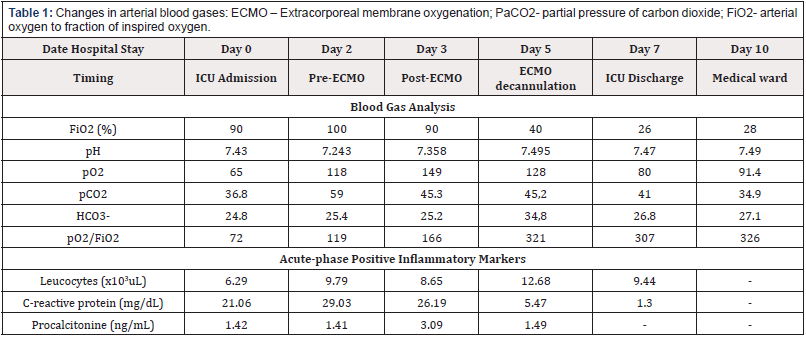

Since the scarce evidence, we can only hypothesize reasons for successful short-term improvement with ECMO support. The singular pathophysiology of tuberculosis-associated ARDS might be one [5], and early treatment may have avoided progression to an organized/fibrotic stage. Timely institution of MV with ultra-low tidal volumes could also have helped preventing ventilator inducedlung injury and minimized lung stress and strain. Repeated BAL sampling and fluid overloading right before cannulation probably played a role in the acute deterioration and rapid improvement once those aggravating factors were corrected, as superimposed bacterial infection, supported by inflammatory markers kinetics (Table1).

Table 1: Changes in arterial blood gases: ECMO – Extracorporeal membrane oxygenation; PaCO2- partial pressure of carbon dioxide; FiO2- arterial oxygen to fraction of inspired oxygen.